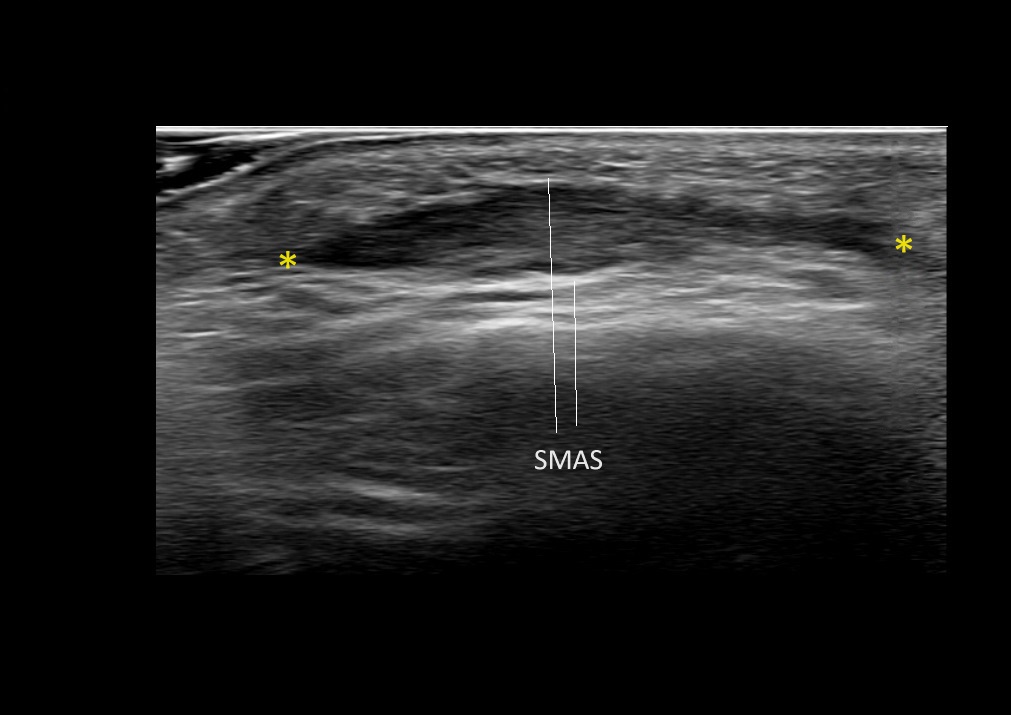

Filler deposits may end up unintentionally in the SMAS or fascial layers of the skin. Very often this will not lead to adverse events, however, adverse events ( nodules, migration / redistribution impaired muscle movement and smiling and malar edema) are are often related to filler ending up in the SMAS or fascia.

Study the first image to recognize the different layers. If you are sure about the layers, swipe to the second image to view the answer (if applicable).